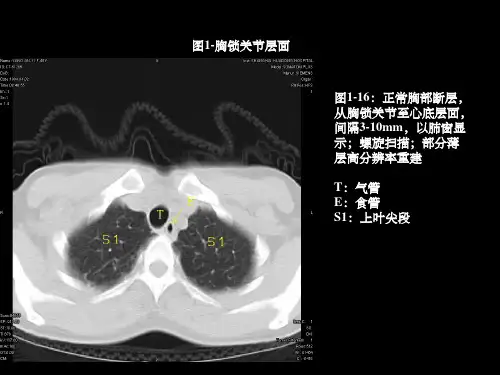

胸部常见病变